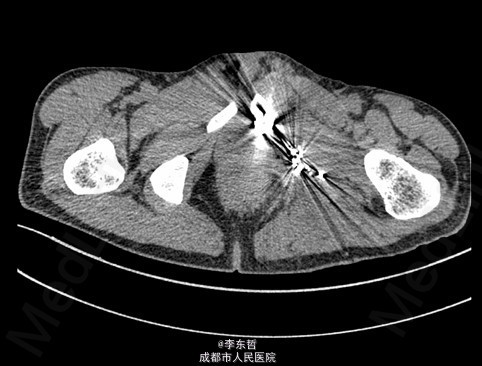

查体:臀部、会阴部、下腹部未触及包块,左下肢前内侧皮肤感觉较对侧减弱,双侧膝反射、跟腱反射正常引出,肛周皮肤感觉减退,直肠指检可触及质韧包块,活动度较差。双下肢肌力5级,双下肢各关节活动度可。 辅查:外院增强CT示:盆腔左侧壁见团块状软组织密度影,密度不均,其内见多发斑块高密度影,病灶大小约9.4*7.6cm,增强后强化不明确。我院X片示:左侧闭孔及耻骨区见不均匀高密度影,大小约6.2*6.7cm。我院MRI示:盆腔左份见长T1长T2肿块影,大小约10.3*7.7*10.5cm,向前推挤膀胱,向右推挤前列腺。我院骨扫描显示:耻骨联合及左侧耻骨支核素浓集。